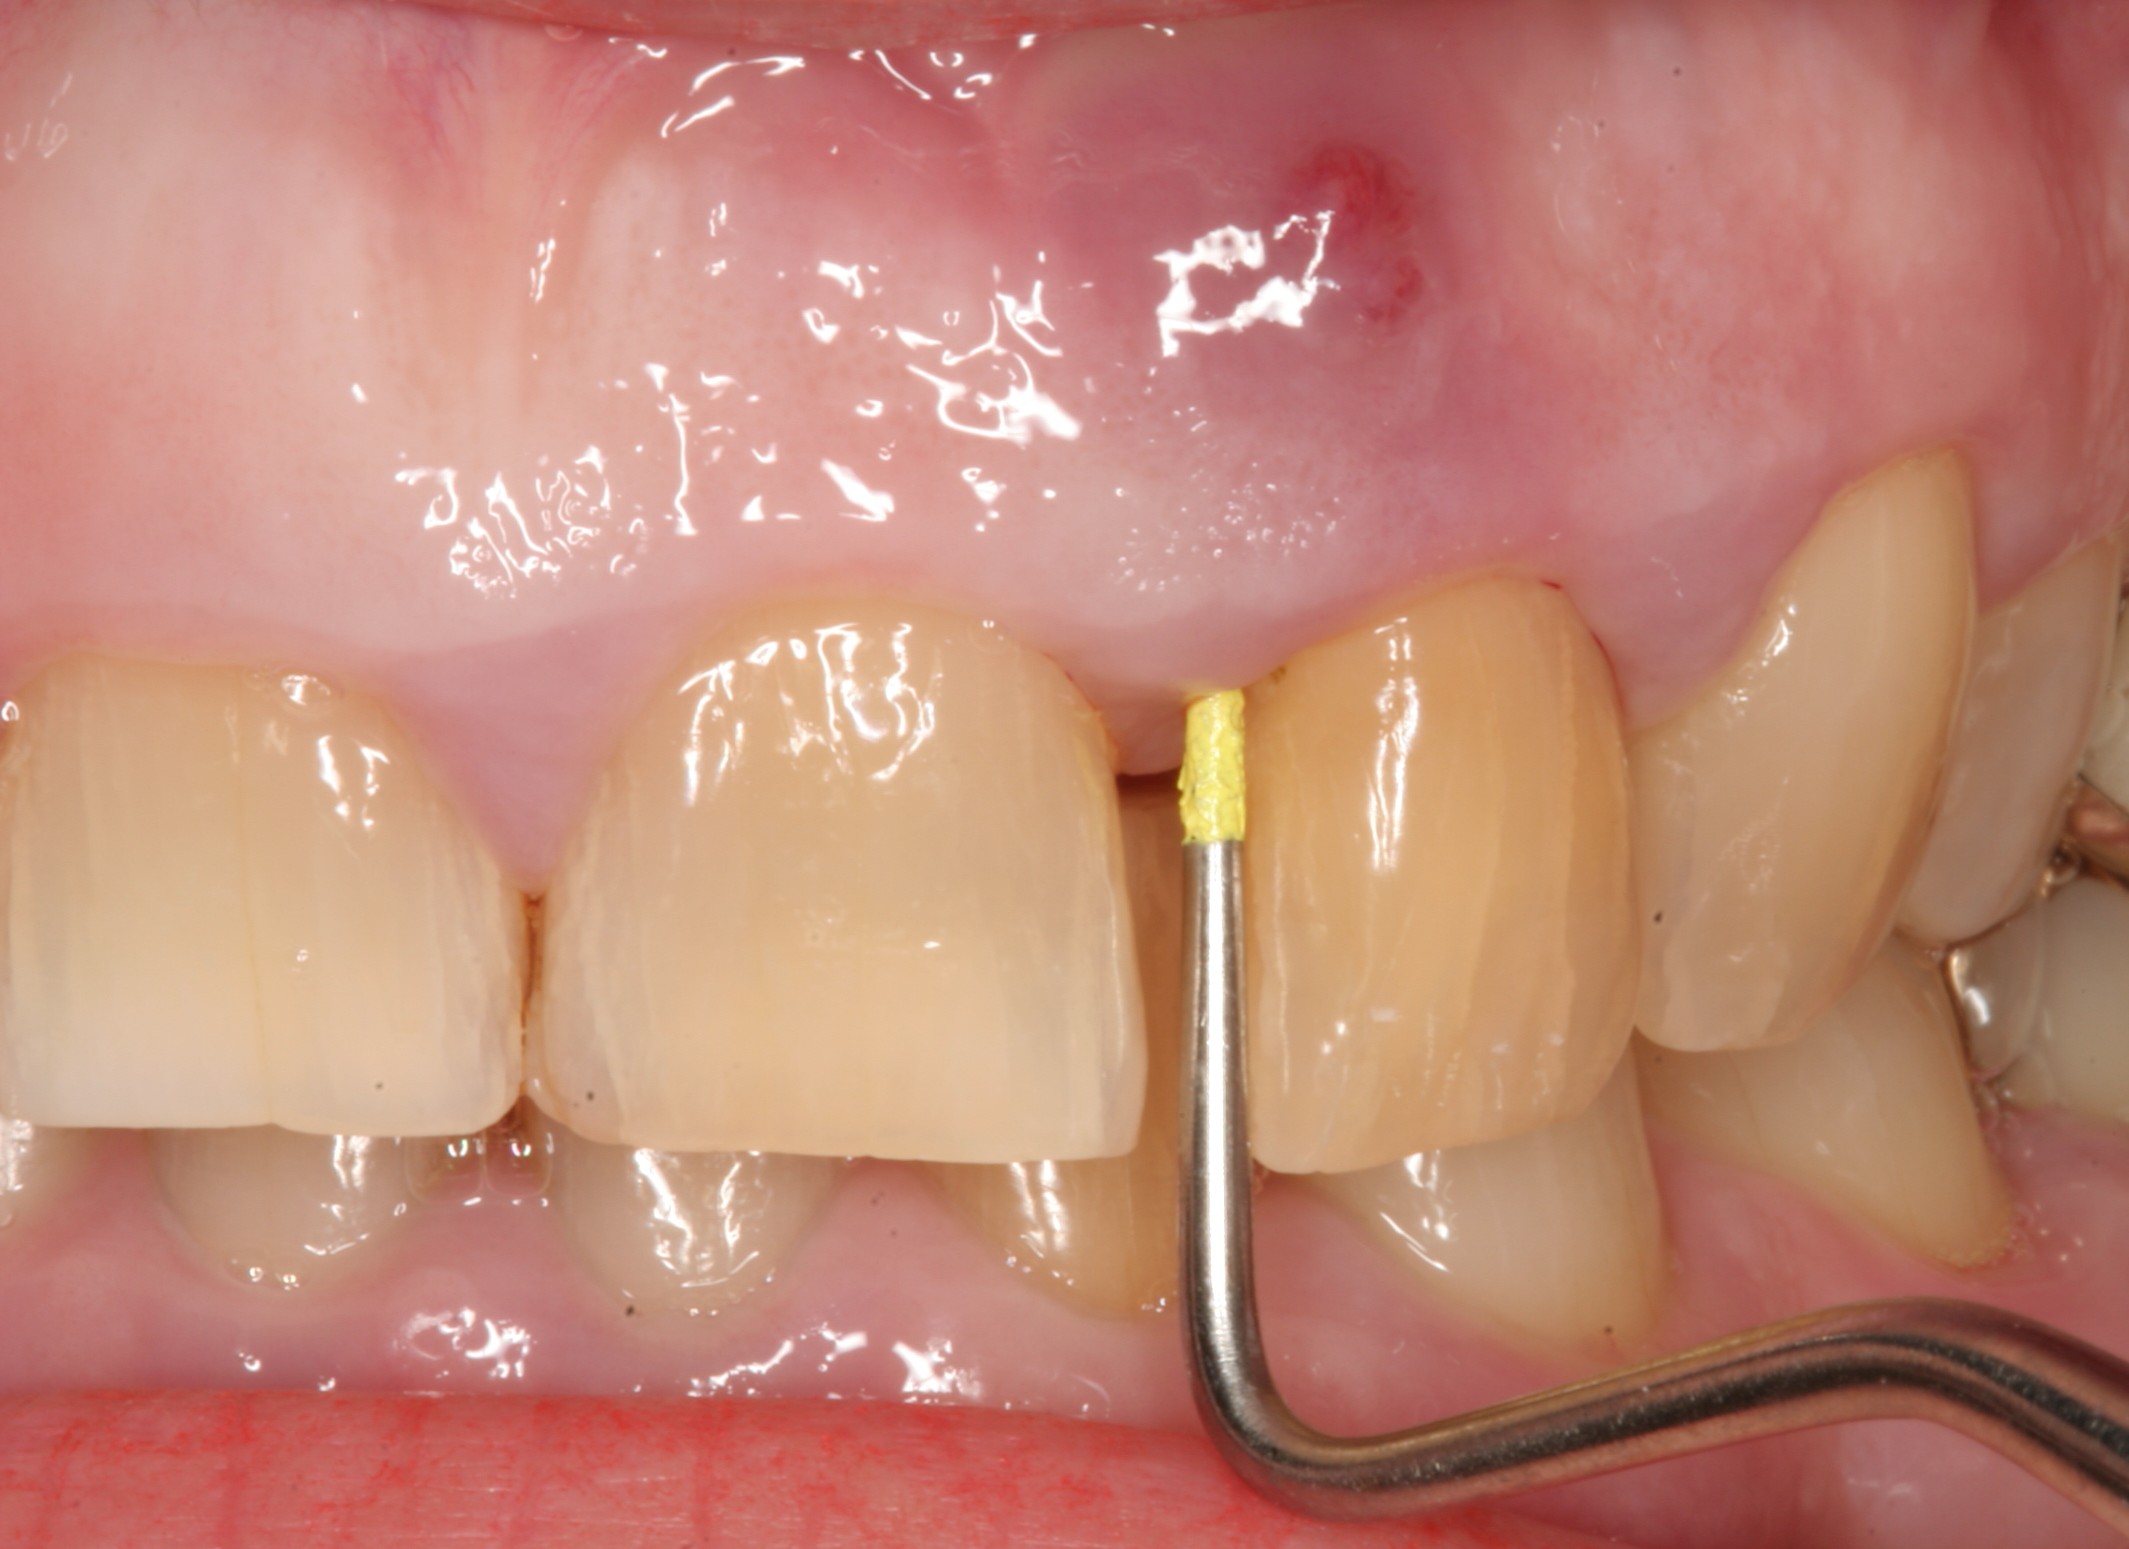

آبسه حاد دندانی چنانچه از نامش پیداست، عفونت حاد در استخوان فک و بافت های نگهدارنده دندان است. علائم آن شامل تورم، درد، گرما در ناحیه، قرمزی، دردناک بودن ناحیه در لمس و حساس بودن دندان به ضربه و دق می باشد. آبسه حاد می تواند دارای علائم عمومی مثل تب و لرز نیز باشد.

به هیچ وجه این کار درست نیست. درمان آبسه حاد دندانی، باز کردن آبسه از طریق دندان یا مخاط است. البته باز کردن مخاط و برش زدن زمانی قابل انجام است که به صورت واضح در زیر مخاط چرک جمع شده باشد. تجویز هر گونه داروی آنتی بیوتیک به وسیله دندانپزشک صورت می گیرد. ضمن اینکه باید توجه داشت مصرف داروی کورتیکو استروئید در زمان عفونت حاد باعث کاهش دفاع بدن و در برخی موارد شدت عفونت می گردد.

درمان آبسه حاد با نظر دندانپزشک انجام خواهد شد. اولین مرحله و مهم ترین قسمت درمان خارج کردن چرک از ناحیه از طریق باز کردن کانال دندان یا برش نسج نرم مخاط به وسیله دندانپزشک است. در صورتیکه چرک از طریق دندان خارج شود پس از خروج کامل چرک و شستشوی دندان، پانسمان کردن دندان لازم است. چرا که باز بودن کانال دندان به محیط دهان باعث اضافه شدن باکتری های موجود در دهان به کانال عفونی می گردد و درمان های بعدی را طولانی تر و با مشکل مواجه می نماید. در صورتی که خروج چرک و باز کردن آبسه از طریق برش در نسج نرم انجام شده باشد، دندانپزشک تصمیم خواهد گرفت که برای خروج ترشحات و چرک مجرا را باز بگذارد یا خیر!